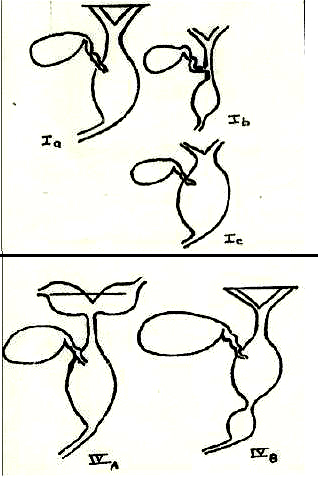

| |

| |

Type I est le

plus souvent a incidenece de 80-90% de

kyste du choledoque . Trois sous type Ia ,

Ib , Ic :

- Ia : Dilatation global

du canal choledoque

- Ib : Dilatation

segmentaire de VBP

- Ic : Dilatation

de voie biliare principale

Type II est diverticule de

VBP |

|

Type III dilatation

VBP a distal ( choledococele )

Type IV Dilatation du canal biliaire

extra et intra hepatique

Type V Dilatation de

voie biliaire intrahepatique ( maladie de

Caroli ) |